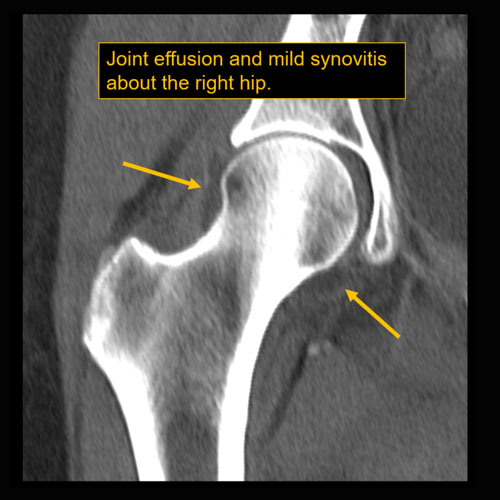

| Visualized Joints | Correct Answer | Your Answer |

|---|---|---|

|

There is a joint effusion. |

No | NA |